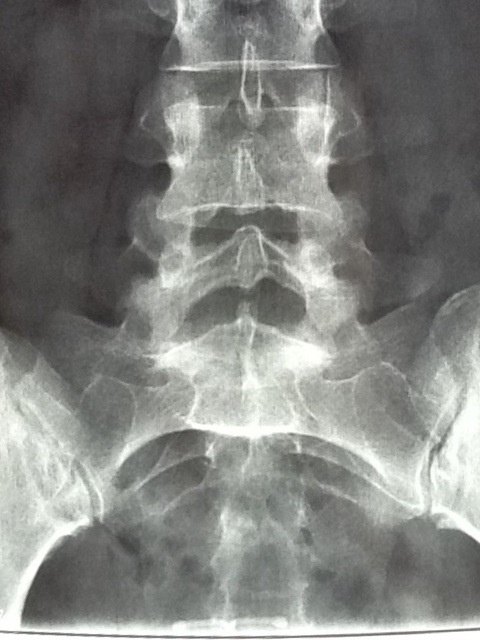

And as it turns out, not very much. I do have one disc that is dried up and cracked and so is squishing out through the crack and bulging a bit. To the right. My nerve issues are nearly all on my left side. Doc couldn’t see any reason that the bulge on the right would be pressing on a nerve on the left. So, surgery was 100% ruled out. Nothing to operate on. He did offer what I had been told were ‘shots’ but actually is an epidural. I agreed, even though I have no idea what they might be pumping into my spinal fluid, and it probably won’t help. If it does, then they know a nerve is indeed being squarshed and that’s a valuable bit of knowledge, to me. Because if the nerve isn’t being pinched at the spine, just what the hell is the issue? Cuz my leg burrrns. Or aches like it is bruised, or itches in a way that can’t be scratched.

Back to the back. Needle in 4-6 weeks, and probably another day off of work. Be interesting to see what result, if any, I get. In the meantime they said my issue appears to be muscular. My lower spine has very little curve to it. Doc said this is because the muscles are supposed to pull tight and make the curve, but mine are weak and haven’t been doing the job. I asked about any options to strengthen the muscles that might be provided by the HSE – none. So Pilates on my iPad it is then, I guess. I can’t afford classes with someone to show me how to do it right – even though I have never done regulated exercises and I doubt I do them right. Only time I ever tried anything close was the Haidong Kumdo and that is what really, really fucked my back up! Even with an instructor. Imagine what I can do to myself, by myself!